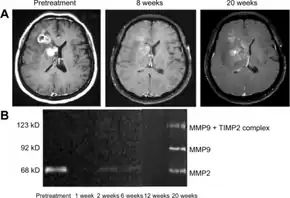

Brain cancers

Bevacizumab slows tumor growth but does not affect overall survival in people with glioblastoma multiforme.[25] The FDA granted accelerated approval for the treatment of recurrent glioblastoma multiforme in May 2009.[26][27] A 2018 Cochrane review deemed there to not be good evidence for its use in recurrences either.[25]